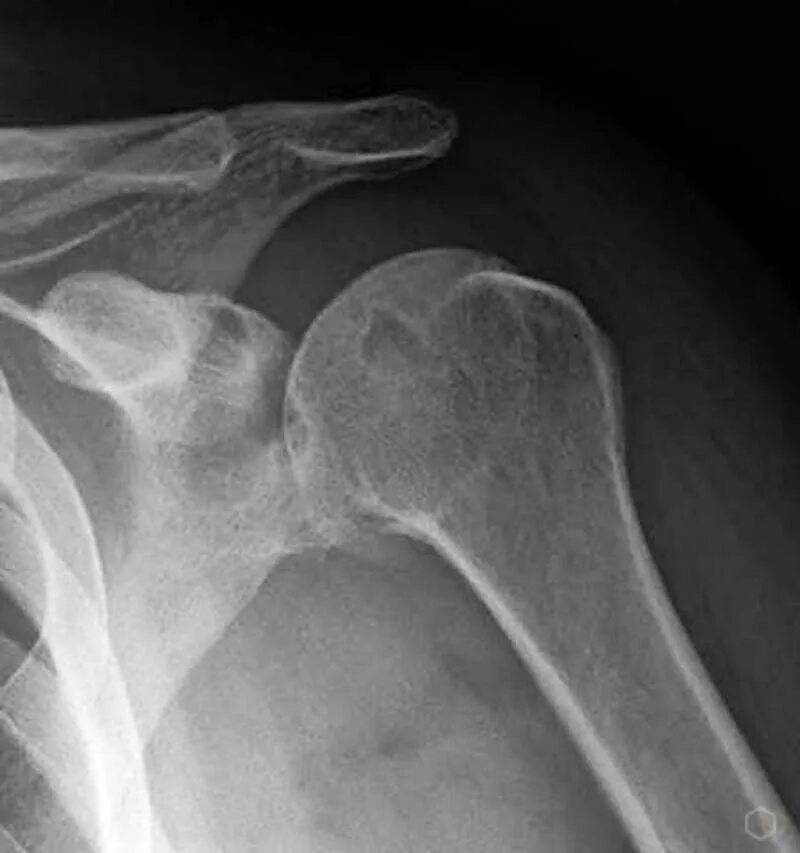

Как лечить артроз плечевого сустава 2 степени